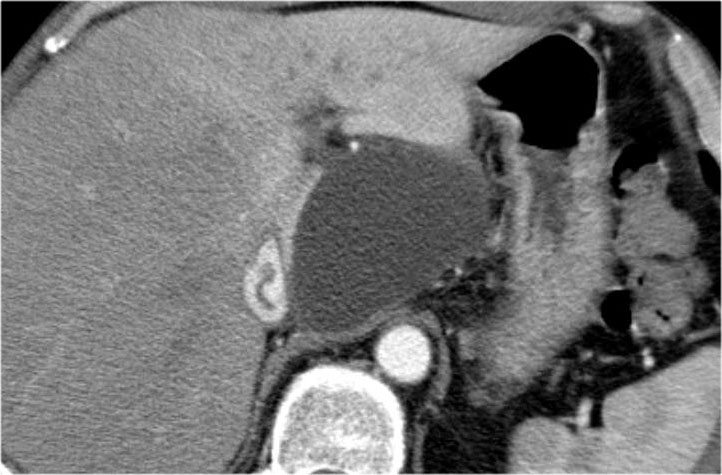

Ở đuôi tụy có tổn thương dạng nang với sẹo trung tâm kèm vôi hóa (mũi tên).

Mặc dù một số nang có kích thước lớn hơn 2 cm, hình ảnh này vẫn điển hình cho u nang tuyến thanh dịch, do có sẹo trung tâm, hình ảnh đa thùy và bờ viền thùy múi.

Bệnh nhân này có các triệu chứng đau bụng được quy cho khối u, khối u đã được phẫu thuật cắt bỏ và kết quả giải phẫu bệnh xác nhận là u nang tuyến thanh dịch.

Đây là bệnh phẩm sau phẫu thuật cắt bỏ.

Khối u dính vào lách, do đó lách cũng phải được cắt bỏ cùng.